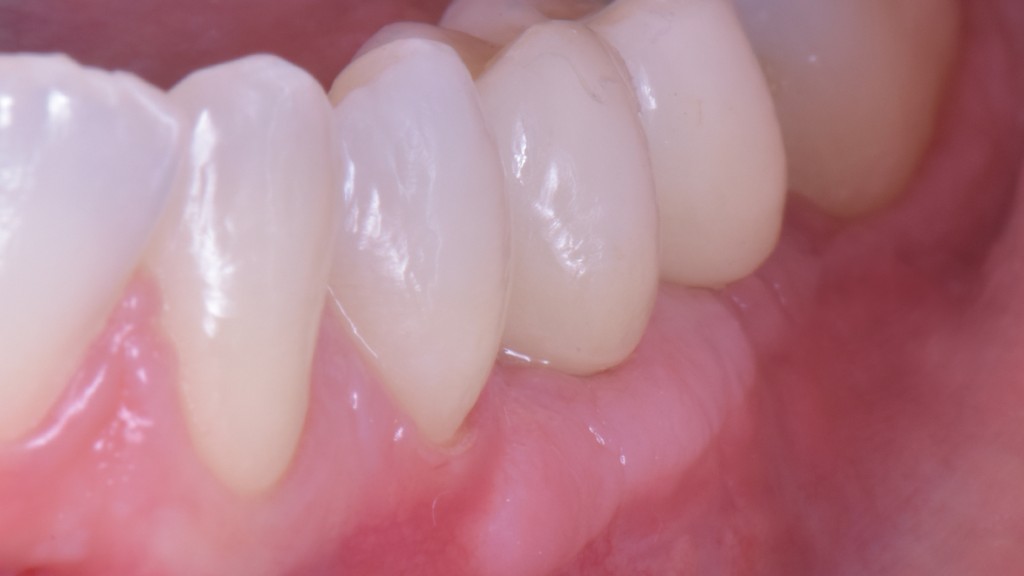

O puoi riabilitare la paziente adeguatamente:

DSC_5588

Ma per fare questo non ci sono polverine magiche di osso di dinosauro o impianti di un millimetro. Ci sono anni di studio, sudore e  sangue (E SGUARONE!!) per noi… e un VAS 2 per la paziente!!!!!!! ?